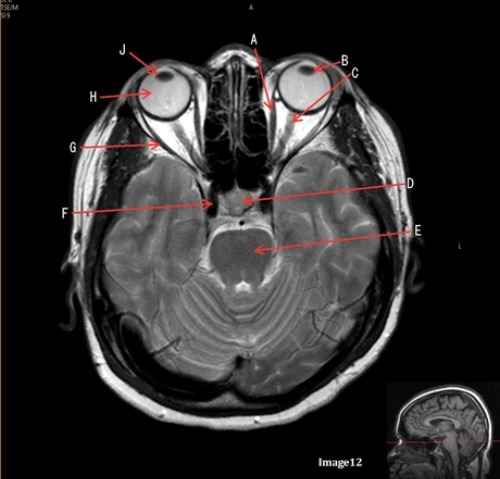

Letter G in Image 12 is pointing to:

A. Lens

B. Lateral rectus muscle

C. Medial rectus muscle

D. Internal carotid artery

E. Globe

Letter C in image 12 is pointing to:

A. Left optic nerve

D. Lens

E. Midbrain

Letter D in Image 12 is pointing to:

A. Optic nerve

B. Pituitary gland

C. Globe

Letter E in Image 12 is pointing to:

D. Pons

E. Left lens

The medial and lateral rectus muscles are located in the:

A. Ears

B. Gluteus maximus

C. Eyes

D. Outer neck regions

Letter A in image 12 is pointing to:

The right and left optic nerve join at the:

A. Optic chiasm

B. Foramen magnum

C. Transverse sinus

D. Internal optic canals

Letter H in Image 12 is pointing to:

Letter B in Image 12 is pointing to:

Letter J in Image 12 is pointing to:

A. Globe

D. Right lens

Letter F in Image 12 is pointing to: